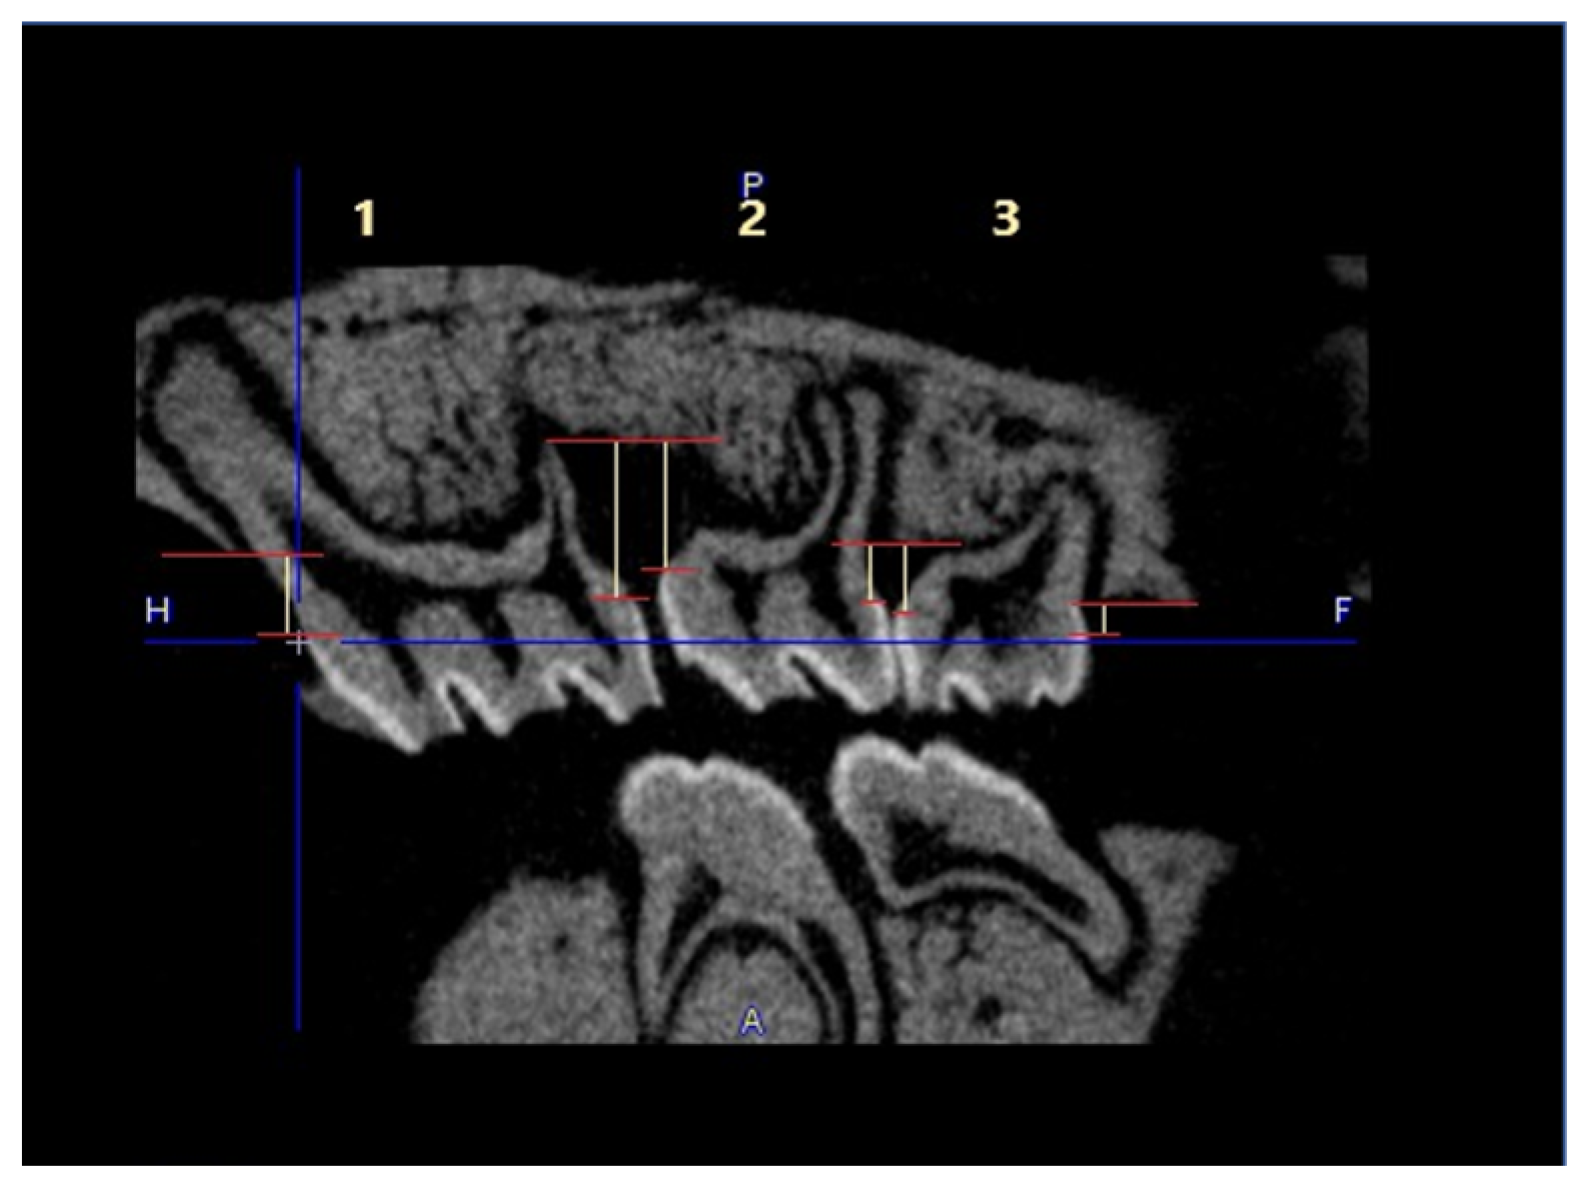

No visible changes were noted in the periodontium. Furthermore, CT scans revealed no alterations in the jawbone area. Due to technical constraints, the experiment was confined to the upper jaw, and alveolar bone loss was quantified using micro-computed tomography (μCT). Measurements were taken from the cemento–enamel junction (CEJ) to the alveolar bone crest (ABC). For each analyzed rat (23 in total), 12 measurements were conducted: three times per molar at two sites (left and right), doubled for statistical replication. The specific distances utilized for statistical analysis are detailed in Figure 8.

Figure 9 presents a representative CT analysis of bone loss in P. gingivalis-infected animals (both minocycline-treated and controls. The beneficial effect of the treatment is clearly visible with regard to bone loss. Comparison of the CEJ-ABC distance shows a significant bone loss in the non-treated animal (A + C, PG), which was remarkably diminished by the treatment (B + D, PG+MIN-T).

This observation has been statistically validated, as shown in Figure 10. Aggregated measurements across all evaluated molars (1st, 2nd, and 3rd upper molars) indicate a significant reduction in bone loss in the treated group PG+MIN-T, with a p-value of <0.0001 compared to the non-treated group (PG). This demonstrates the antibiotic’s effectiveness over 31 days following treatment with the novel formulation.

To determine bone loss High Resolution Animal Computed Tomography (Micro-CT, MILabs, The Netherlands) was used. All animals were scanned at two time points (before treatment (T0) and on the day of termination of the experiment (TEND)). Imaging was performed at an ultra-focus magnification, 50 kV source voltage, and 0.21 mA current. Three-dimensional images were obtained using the PMODE software (vers. 4.3; Fällanden, Switzerland). To assess the alveolar bone loss, a linear distance from CEJ to ABC of each tooth of the lower and upper jaw was measured. Each measurement was performed three times, and the data are presented as the mean ± standard deviation (SD). The results are presented as the distance after subtracting the basal measurement (T0) from the measurement obtained at the endpoint of the procedure (TEND).